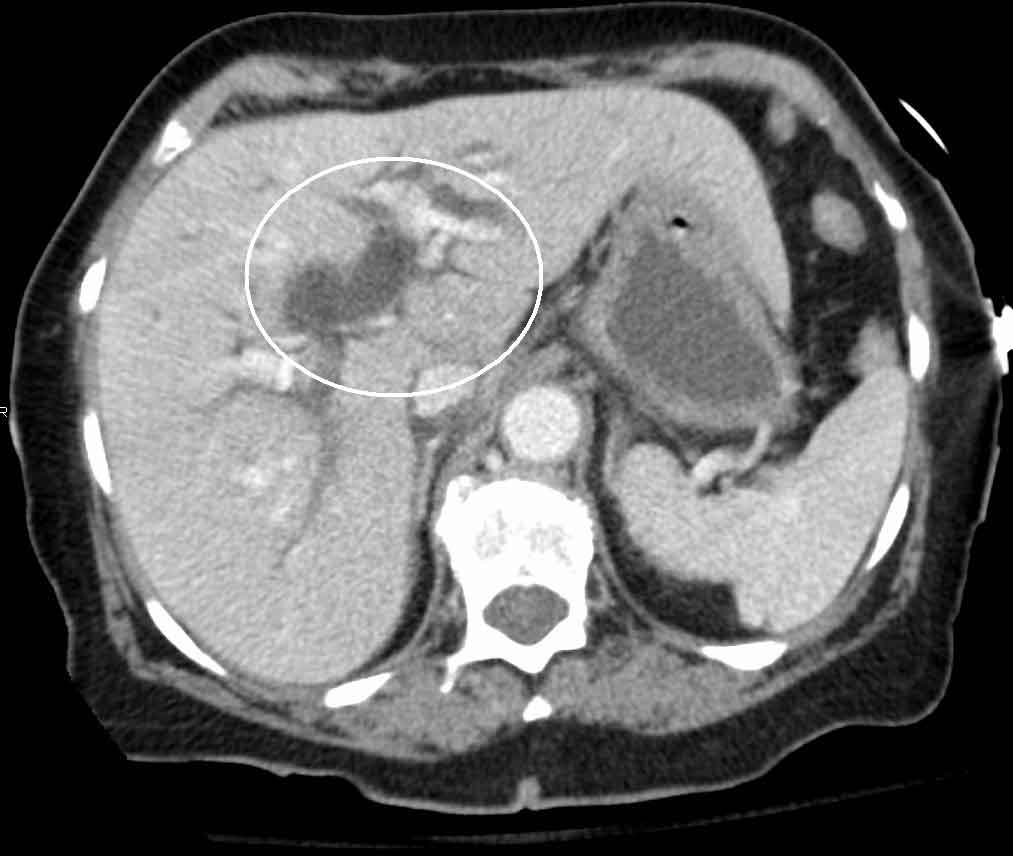

Imaging showing dilated common bile duct due to obstructing gallstone

Complications & Planning

CT Abdomen

Used when complications are suspected — perforation, abscess, pancreatitis, or when surgery needs detailed anatomy. Not the first-line test for simple gallstones, but invaluable for emergency and complex cases. Blood tests (LFT, amylase, CBC) are essential companions to all imaging.